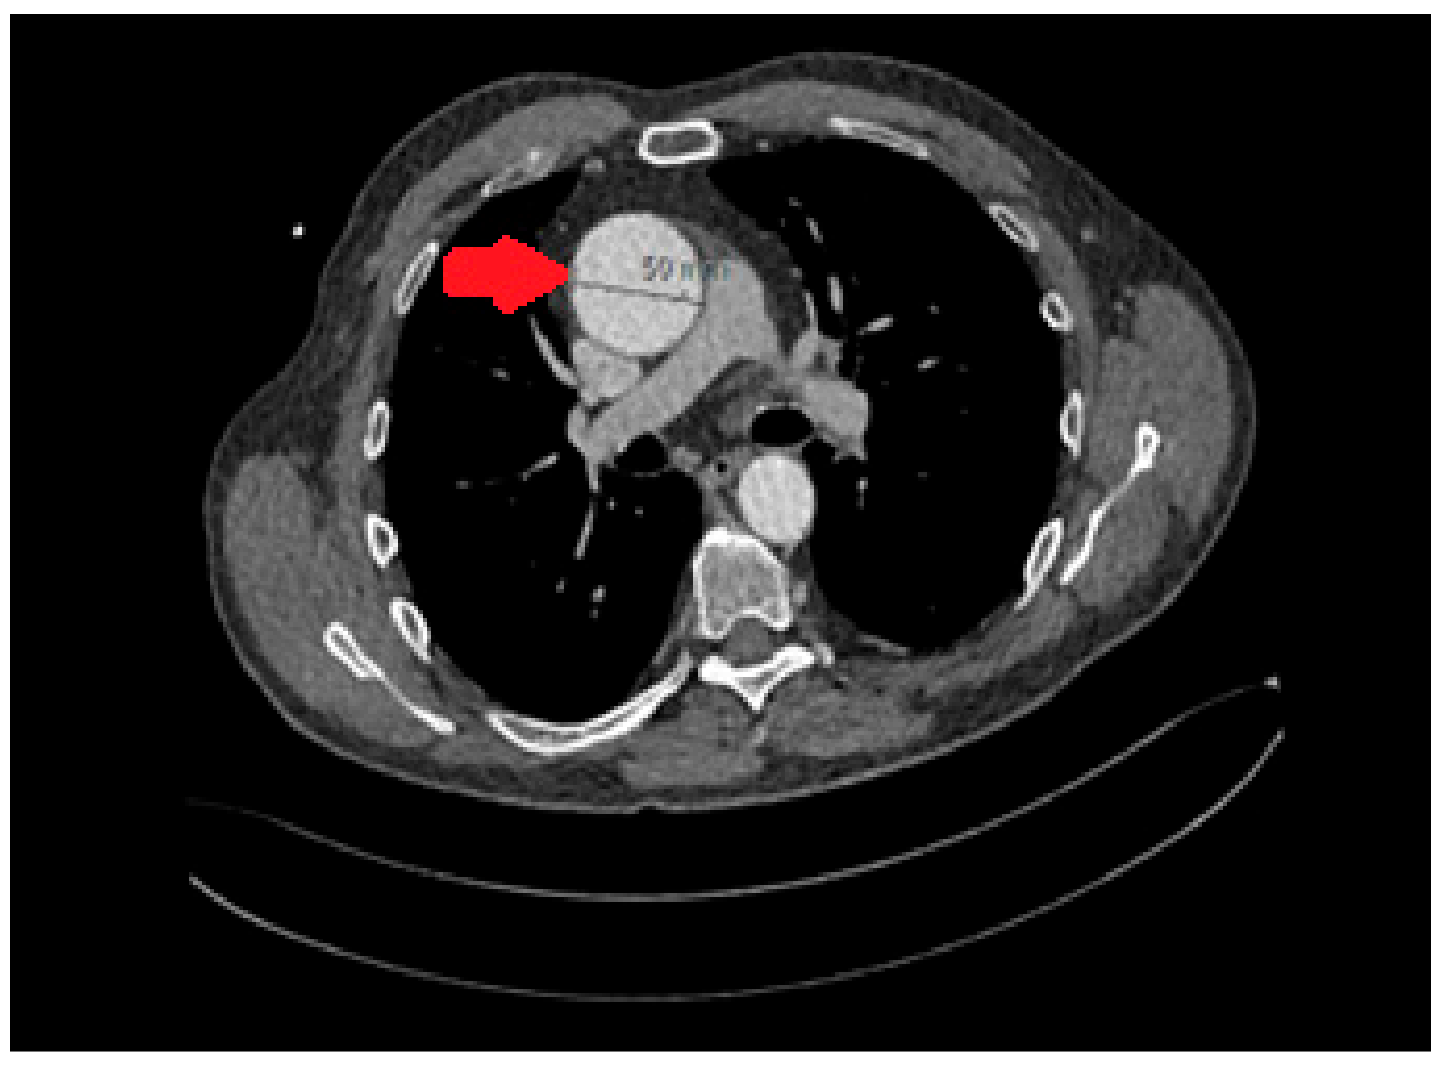

A transesophageal echocardiogram (TOE) identified a collection around the aortic root. CT thorax (Figure 2) confirmed bilateral lung consolidation and a small hematoma collection around the aortic root in keeping with recent surgery. As it was possible that the cardiac arrhythmias and hemodynamic instability were related to the peri-aortic hematoma, the decision was made to proceed with a re-sternotomy and drainage. This was performed on postoperative day thirteen with drainage of a moderate serous pericardial effusion and evacuation of the periaortic hematoma. An intra-aortic balloon pump was also inserted.

Figure 2. A CT scan of the chest showing hematoma collection around the aortic root (arrow).